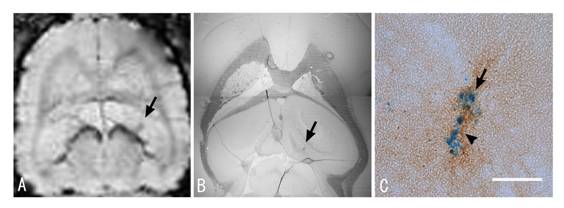

図5

図5 アルツハイマー病モデルとミクログリア

A.ラット脳のT2*−強調MR画像(水平断)、B.組織化学画像とC.その拡大図(スケール・バーは50μmを表す。)

βアミロイドが投与された部位(矢印)に常磁性標識されたミクログリア(静脈から投与)が集積していることを示す。βアミロイドの反対側には生理食塩水がコントロールとして投与されている。B.はMR画像(A)に対応する組織画像でMR画像のコントラストが得られる部位に鉄粒子で標識されてミクログリアの集積が観察された。C.Bの拡大図でアミロイド(茶色)の沈着した部位にミクログリア(青色)が集積している。

βアミロイドを投与した部位は図5のAのラット脳のMR画像の矢印の部位で、その反対側にはコントロールのために生理食塩水を投与した。この処置を施した3日後に、レゾビストで標識したミクログリアを静脈から導入し、その1日後にMR画像を撮像した(図5A)。この画像はラット脳のT2*−強調MR画像(水平断)を示す。この画像から、βアミロイドが投与された部位(矢印)に常磁性標識されたミクログリア(静脈から投与)が集積していることを示す。一方、生理食塩水が投与された反対側にはこのような集積は観察されなかった。このMR画像に対応する組織化学の画像とその拡大を図5BとCに示した。MR画像のコントラストに対応する部位に鉄粒子で標識されたミクログリアが集積していることが確認でき、MR画像と良い一致を見せる。図5の拡大図では、βアミロイドが高濃度に蓄積した部位(茶色)に標識したミクログリア(青色)が集積している。このミクログリアが実際にアミロイドを除去しているかどうかは不明ではあるが、少なくとも貪食作用を持つミクログリアが特異的に集積することがMR画像で確かめられた。ミクログリアの働きを利用してβアミロイド沈着を取り除くというアルツハイマー病の新しい治療戦略にも期待が持てそうである。